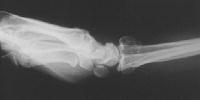

Clinical Example: Distraction plate fixation of distal radius fracture

A tricky case, for the patient previously had a large skin graft over the dorsal metacarpus / wrist / forearm. Incisions are marked here just before the plate was removed.